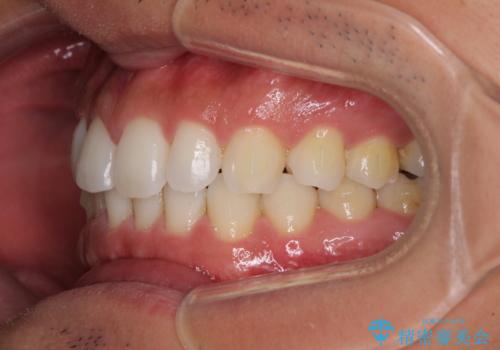

- 上下前歯のデコボコを気にして来院された患者様です。

以前矯正をした後戻りということで、歯列不正はそれほど大きくなかったため、インビザライン・ライトを用いて矯正治療を行うこととしました。

1日22時間以上しっかりと装着してくださったので、半年かからずに治療を終えることができました。